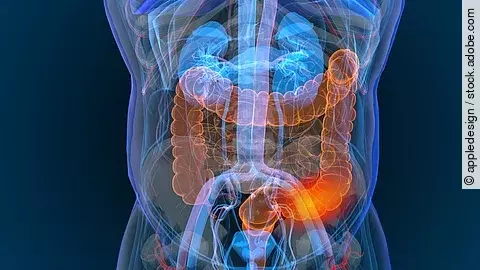

Etwa die Hälfte aller Patientinnen und Patienten mit einem kolorektalem Karzinom entwickelt im Krankheitsverlauf Lebermetastasen. In bis zu 20% der Fälle finden sich diese bereits zum Zeitpunkt der Erstdiagnose. Für das therapeutische Management der Lebermetastasen kommt routinemäßig eine kontrastmittelverstärkte Mehrschicht-Computertomografie (CT)…

Über die letzten 2 Jahrzehnte wurde das Management kolorektaler Karzinome (CRC) kontinuierlich aktualisiert und verbessert. Jetzt versuchten Wissenschaftler aus Dänemark die Rezidivhäufigkeit bei Darmkrebs entsprechend der Stadien besser abzuschätzen. Dafür werteten sie die Daten von über 34.000 Personen mit Darmkrebs aus.